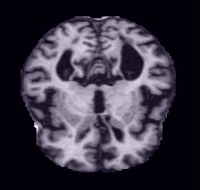

Monitoring the progression of Alzheimer's disease:

Monitoring the progression of Alzheimer's disease:

Our AI is able to detect early signs of Alzheimer's disease and track its progression, providing doctors with valuable information to adjust treatments and slow progression.